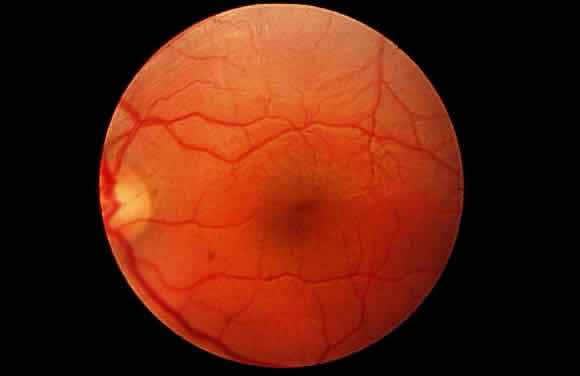

Progressive corneal clouding may prevent visualization of the fundus, but signs of retinal involvement and optic atrophy have been documented in Hurler syndrome. Gills and coworkers reported the absence of the foveal reflex and optic atrophy in several patients.21 In addition, the fundus appeared “albinoid” in one, and the retinal arterioles were narrowed in another. The electroretinogram (ERG) is abnormal, usually markedly reduced, in Hurler syndrome.21–23

The principal ophthalmologic manifestation of MPS II is progressive retinal degeneration with attendant impairment of vision.21,51 Night vision problems and visual field defects are common. The disorder may lead to blindness. The fundus signs include retinal pigmentary changes, sometimes spicule formation, retinal arteriolar attenuation, and optic disc pallor. The ERG is usually reduced or extinguished21,22,52; in some cases it is normal.22 In addition, bilateral epiretinal membranes with tortuosity of the retinal vessels has been reported as an unusual finding in two brothers with Hunter syndrome type B.53

In their histopathologic study of the eye by light microscopy in type B Hunter syndrome, Goldberg and Duke found few corneal abnormalities.48 The corneal epithelium and Bowman's layer were intact, except peripherally where Bowman's layer was split and where eosinophilic material was present beneath the epithelium. Descemet's membrane and endothelium were intact, although eosinophilic granules were present in the endothelial cytoplasm. Fine granular deposits were present in the corneal stroma, chiefly in interlamellar spaces. The nonpigmented epithelium of the ciliary processes appeared foamy. There were significant retinal changes, including pigment migration, paucity of pigment epithelial cells, diminution of rods and cones, reduction in number of ganglion cells, and gliosis of the nerve fiber layer. The sclera was thickened.